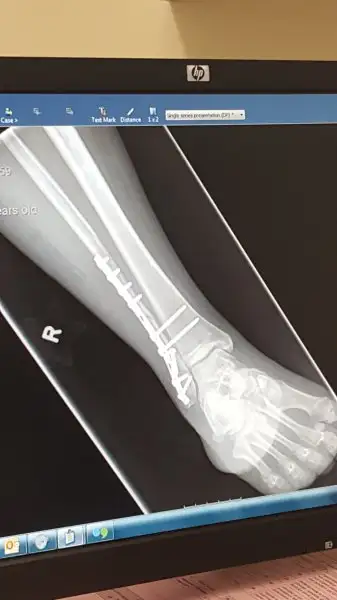

Belki aranizda bilenler vardir.Ben gecen ay merdivenlerden dustum ve ayak bilegi ve bacagimda coklu kiriklar oldu.Ameliyat oldum,platin ve 8 tane vida takildi.40 gundur alcidaydi bugun cikarildi alci.

Vidalarin ikisi alinabilir 6 ay sonra dediler ama oda mecbur degilmis..rontgen cekildi bugun doktor kiriklar iyi durumda dedi.O ozel cizmelerden verdiler 4-6 hafta kadar onunla yavas yavas basabilirmisim..

Fakat eve gelince birsey dikkatimi cekti rontgen filminde.Doktor iyilesti dedi ama kirilan yerde ben hala kirik goruyorum sanki..yoksa iyilesti de kemigin kaynadigi nokta oyle mi gorunur normal olarak bilemiyorum..keske doktorun yaninda fark edip sorabilseydim.Gerci 8 hafta sonra birdaha rontgen cekilecek..

Arada o cizgi olur ancak 4 5 ayda tam kaynar

Tam kaynamış hali bile hiç kırılmamış gibi olmayabilir.

Yani kısaca bi sorun yok